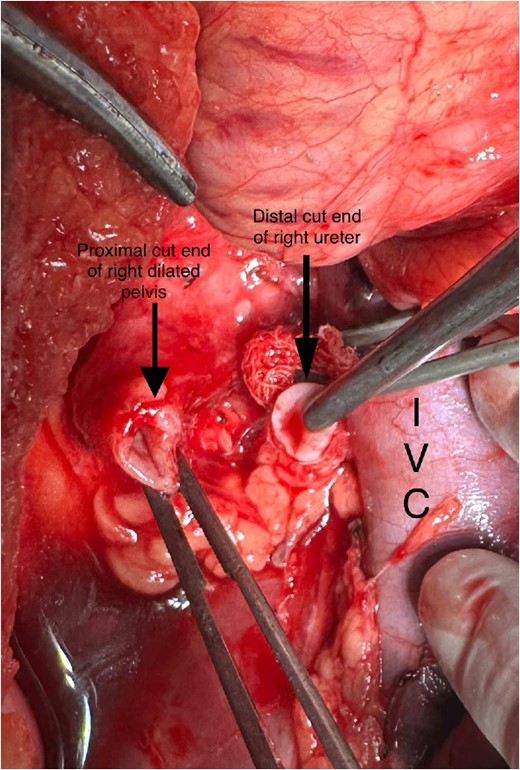

A midline incision was given, and the abdomen was opened from 4 cm below the xiphisternum to 3 cm above the pubic symphysis. The ascending colon along with the hepatic flexure was completely mobilized medially to expose the retroperitoneum. Careful dissection was done to identify the IVC and its the relations to the right ureter. The proximal dilated ureter and right pelvicalyceal system were identified, and dissection was continued laterally. The ureter was traced and noticed to course behind the IVC at the level of the L2–L3 vertebra, exiting to lie medially in the groove between the IVC and the aorta (Fig. 3). The ureter was divided proximal to the point where it coursed behind the IVC until it came out medial to IVC (Fig. 4). The retrocaval segment was brought anteriorly, resected from the normal distal ureter, and ureteropelvic anastomosis was done using 3–0 Polyglactin sutures lateral to the IVC (Fig. 5). This procedure eliminated the compression on the ureter. An abdominal drain was placed.

Intraoperative image showing the course of the retrocaval ureter and the important structures around it.